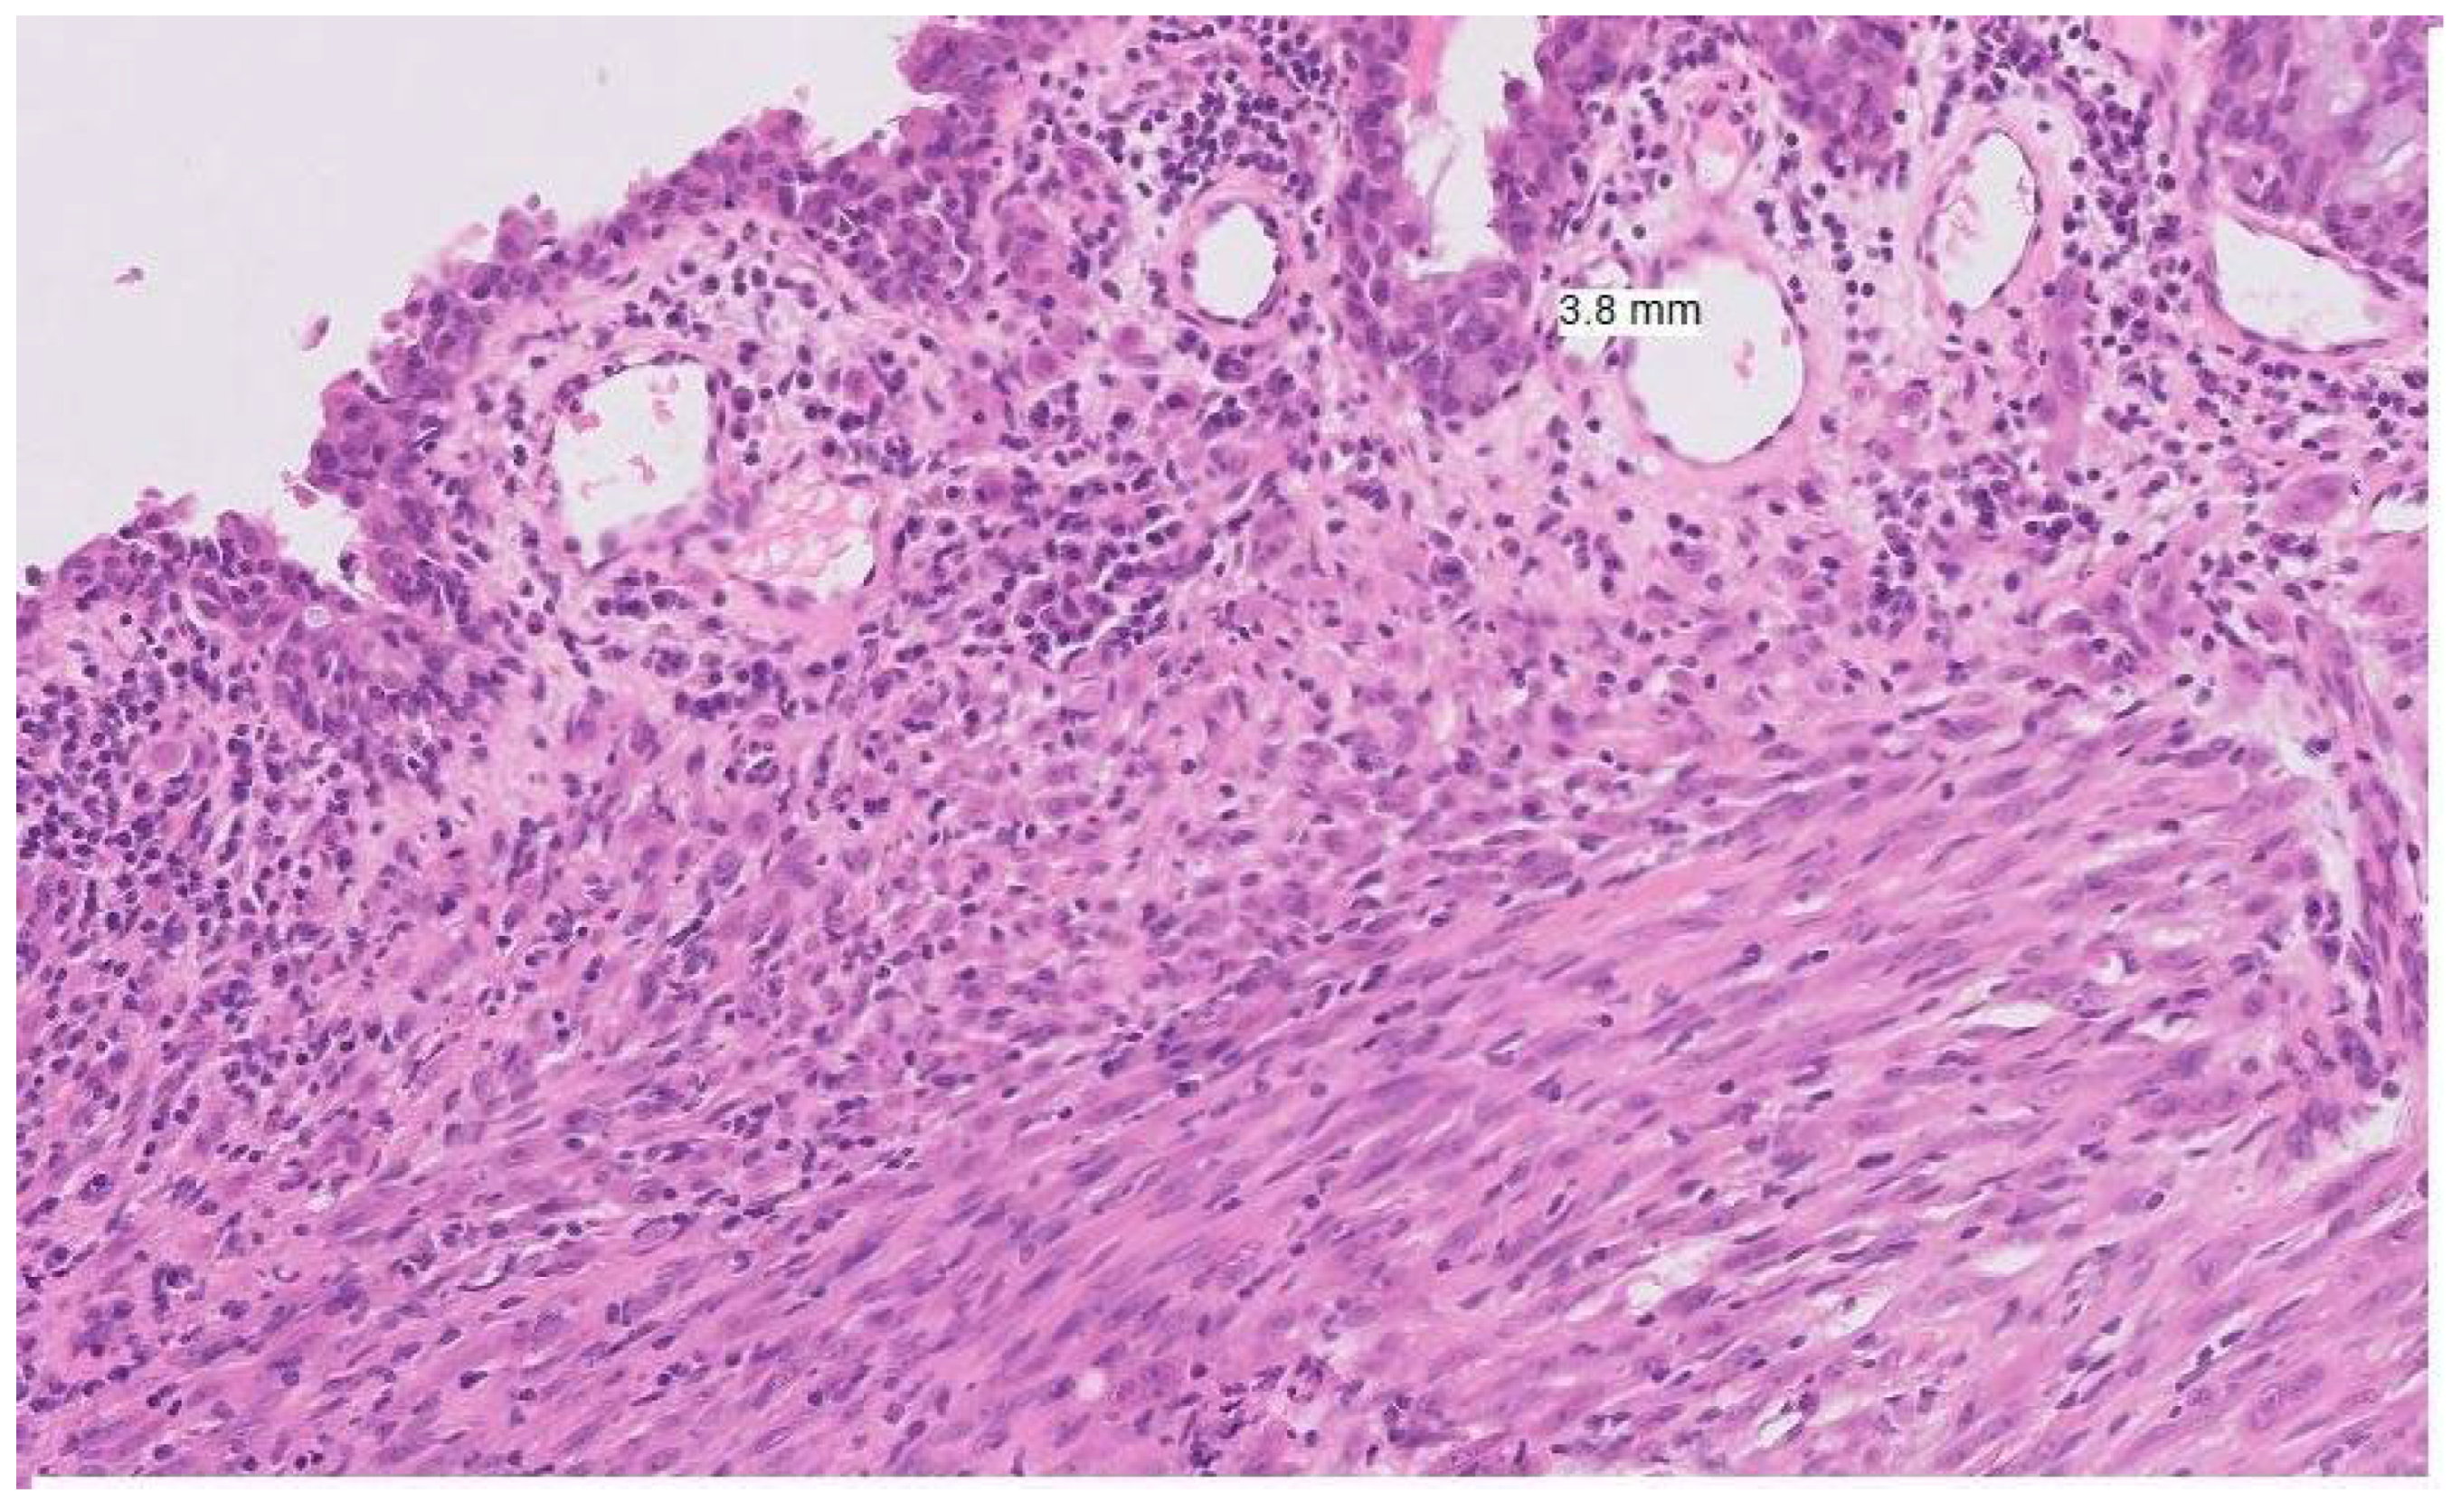

Figure 2. Histopathological Features for (a) Vulval Melanoma; Sections show a pigmented melanocytic lesion with evidence of junctional activity, marked cytological atypia, and invasion into the deep dermis. Growth is seen in both radial and vertical phases, with a brisk mitotic rate and perineural invasion. Melanin pigment is present within tumour cells. (b) Vaginal Melanoma; The tumour shows a polypoid architecture, often pigmented, with satellite nodules. Microscopy demonstrates solid, nested, and trabecular patterns, with a radial growth phase and brisk mitotic activity. Melanin is frequently present. Immunohistochemistry highlights S100 as the most sensitive marker.

Emerging evidence highlights the distinct molecular profile and tumour microenvironment seen in vulvovaginal melanoma, with variation evident even between vulval and vaginal sites. KITKIT mutations are more common in vulval melanomas (22–31% of cases) compared with vaginal melanomas (8%) [22,23]. Conversely, NRAS mutations are uncommon in vulval melanomas (10.2%) and appear to have a comparatively higher incidence in vaginal melanomas [22,23]. BRAF mutations are significantly less common in vulvovaginal melanomas, and TERT mutations may be entirely absent. Other frequently mutated genes include ATRX, SF3B1, B2M, NF1, and TP53 [23]. In terms of immunogenicity, vulvovaginal melanomas demonstrate lower rates of PD-L1 positivity (18%) compared with cutaneous melanomas (29.5%) and overall reduced expression of immune checkpoint genes. They also have a lower tumour mutational burden, in contrast to 46.9% of cutaneous melanomas, which display a high tumour mutational burden [23]. RNA deconvolution analysis of the tumour microenvironment further demonstrates reduced adaptive immune responses and decreased immunogenicity, with lower infiltration of immune-promoting macrophages, effector CD8+ T cells, and CD4+ T cells [23]. These distinct mutational and immune characteristics highlight vulvovaginal melanoma as a unique subclass of mucosal melanoma and may help explain its differential responses to systemic melanoma therapies (See Figure 2).